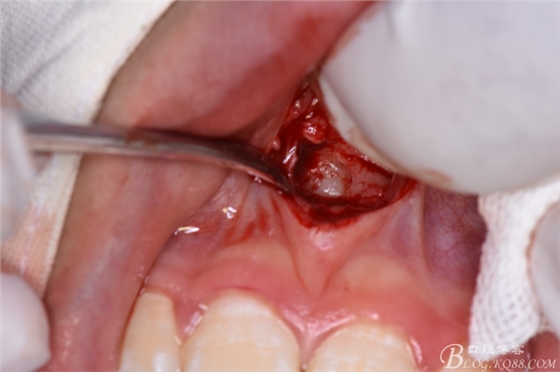

圖20. 在12、13根尖所對應(yīng)的前廳溝處做第二個弧形切口

圖21.一定要切透粘骨膜。

圖22.翻瓣、暴露骨面

圖23.去骨、暴露出鼻底下方的倒置多生牙。